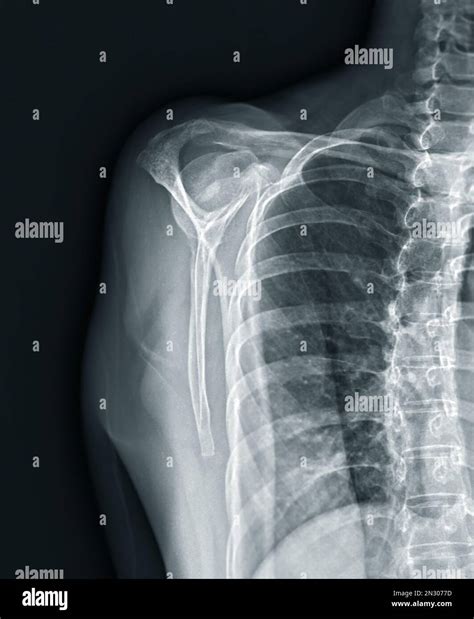

Scapular Y View

The scapular Y view, also known as the scapular lateral view, provides a clear image of the glenohumeral joint and the scapula. It is named for the Y-shaped appearance of the scapula in this view. This view is helpful for evaluating fractures of the scapula and assessing the alignment of the glenohumeral joint.